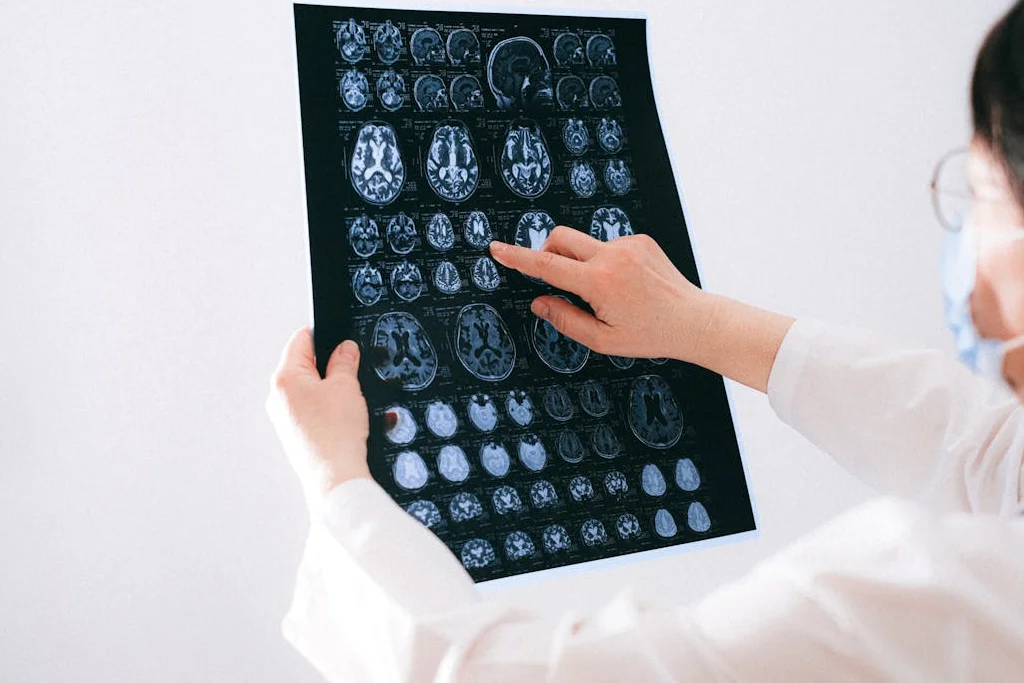

Neurology

Expert neurological care for brain and nervous system disorders with state-of-the-art imaging technology.